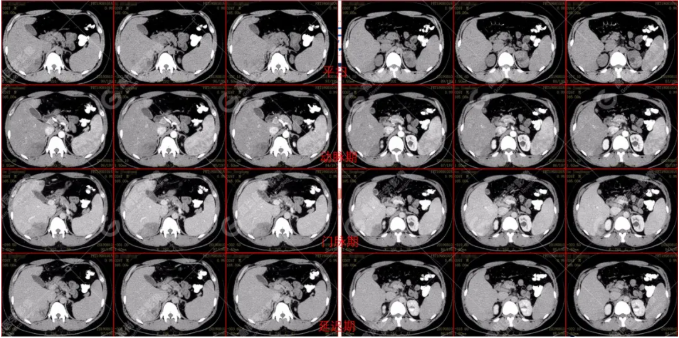

B超及CT檢查發(fā)現(xiàn):肝臟多發(fā)低密度占位。

吡喹酮治療前兩天體溫驟然升高,之后體溫恢復(fù)正常,半個月后CT復(fù)查肝臟病變體積較前明顯縮小、吸收。